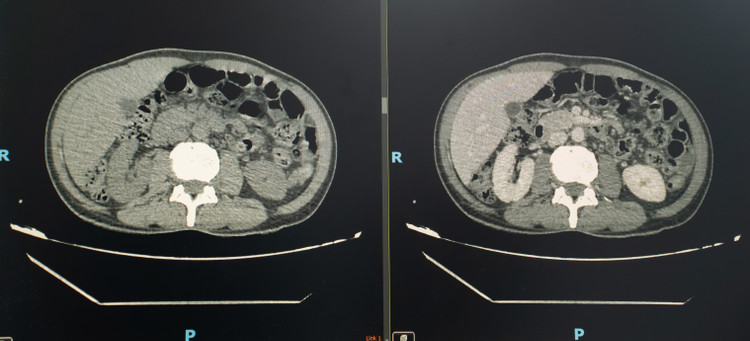

Hình ảnh dị vật trên phim chụp - Ảnh BVCC

Khi tiến hành siêu âm kỹ hơn, ê-kíp phát hiện một dị vật cản quang xuyên trong nhu mô gan, chiều dài ước tính khoảng 6-7cm. Ngay sau đó, bệnh nhân được chỉ định chụp cắt lớp vi tính (CT scan) ổ bụng.

Kết quả cho thấy có một dị vật dạng que dài nằm hoàn toàn trong nhu mô gan, kèm theo ổ áp xe sâu. Trước nguy cơ biến chứng nặng nếu không điều trị kịp thời, ê-kíp khoa Nội tiêu hóa đã nhanh chóng hội chẩn cùng khoa Ngoại Gan Mật Tụy, thống nhất phương án phẫu thuật lấy dị vật, dẫn lưu ổ áp xe, kết hợp điều trị kháng sinh phù hợp.